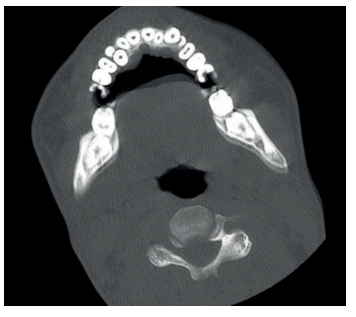

Los casos de osteonecrosis mandibular son frecuentes en pacientes con MPS tipo III y en algunos de los casos el diagnóstico se realiza en fases avanzadas por CBTC rutinarios, como mencionan Koehne y cols.30.

Cuando comienzan el recambio dentario, se debe mantener continuas revisiones odontológicas, puesto que en estos casos existen problemas para la exfoliación de los dientes deciduos. Se pueden encontrar dientes supernumerarios e inclusiones dentarias, que serán extraídos por un especialista en quirófano bajo sedación profunda, debido a la alteración cognoscitiva importante que suelen presentar y/o hiperactividad en fases intermitentes39 (Figuras 9, 10 y 11).

En los casos más avanzados resulta muy complicado realizar la exploración radiológica de manera convencional, por lo que se puede optar por TC, donde el paciente es acomodado utilizando posicionadores específicos, e incluso proceder a la sedación en ámbito hospitalario.